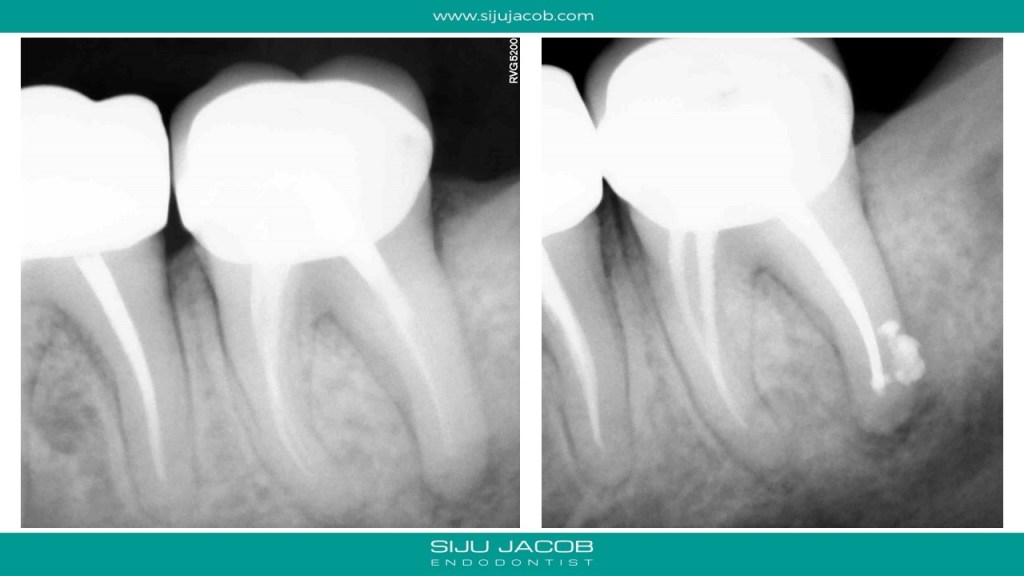

In the past, when we attempted Re-treatment, we used to re-treat all the canals. For the past 4-5 years, I’ve been doing mostly selective Re-treatment ie: treat only those roots or canals which need something to be done. Michael Trudeau calls it “Titrated Treatment”. Some of my friends call it “Image guided Treatment (IGT)”.

This patient had pain followed by a sinus tract on a previously endo treated and crowned mandibular second molar. The Distal root had a lesion. The Mesial root, although short, didn’t have any lesion. So, I decided to leave the mesials alone. I placed Calcium hydroxide, waited for the sinus to heal and then Obturated.